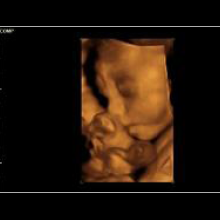

Eine ganz besondere Faszination bieten die neuen 3D/4D Ultraschallgeräte.

Die 3D-Sonografie erlaubt die einzigartige räumliche Darstellung des ungeborenen Kindes. In der 4D-Technik werden Bewegungsabläufe in nahezu fotorealistischer Weise in Echt-Zeit (Real-Time) mit bis zu 25 Bildern/sec. möglich- ein faszinierender Einblick in die Welt des Ungeborenen.

HIER EINE AUSWAHL VON 3D-ULRASCHALL-BILDERN:

Die digitale Verarbeitung ermöglicht die Rotation in jeder Richtung und die Anfertigung von Schnittbildern in jeder Ebene. Wir führen 3D/4D Ultraschalluntersuchungen im Rahmen unserer Wahlleistungen (IGeL) durch.

Wir beraten Sie gerne, bitte sprechen Sie uns an. 3D/4D-Ultraschall-Untersuchungen sind deutlich mehr als "Baby-TV".